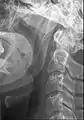

Ossified stylohyoid ligament or elongated styloid process